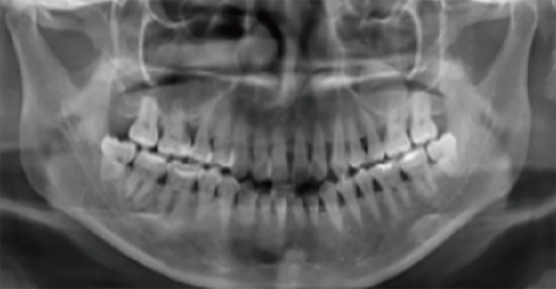

Analysis of oral X-rays for VinciSmile invisible orthodontic treatment

1.The role of panoramic X-ray in invisible orthodontic treatment

4.Influence of CBCT in the field of oral treatment

Application of CBCT in invisible orthodontic treatment

1.The role of CBCT in orthodontics